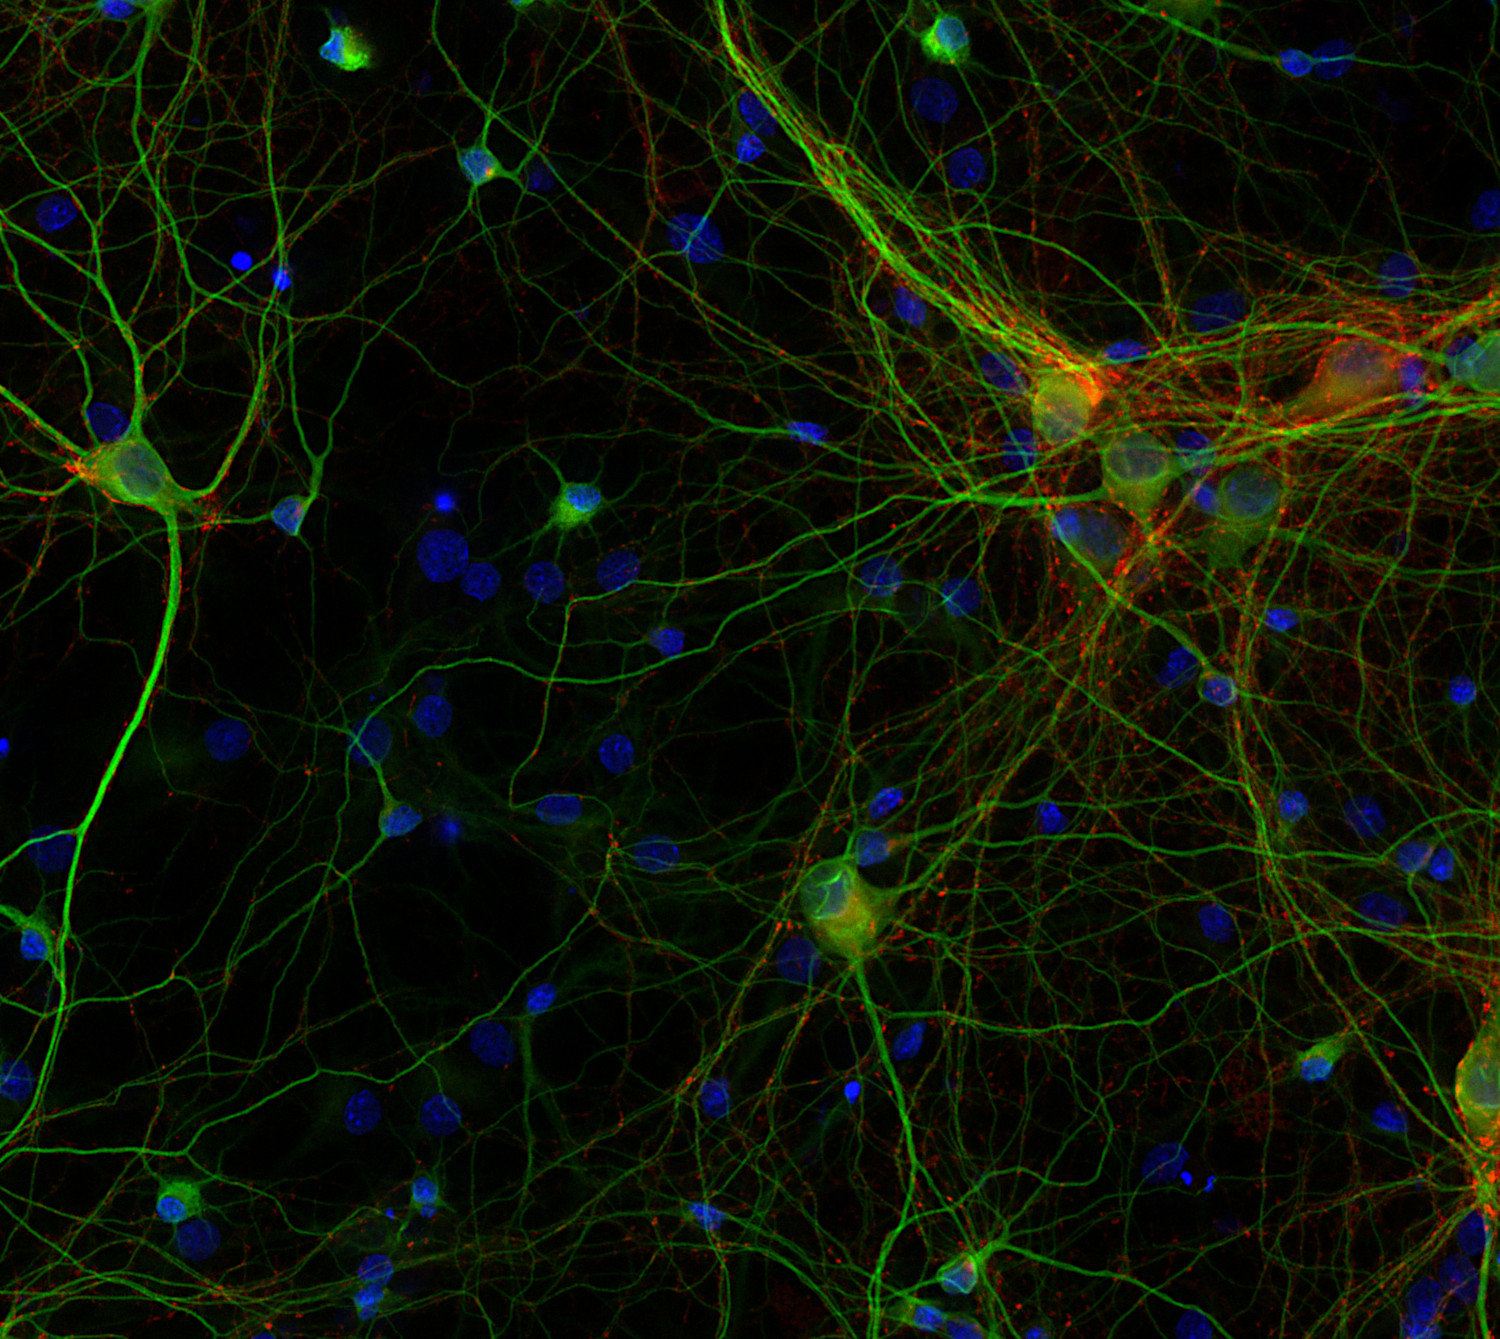

RNA Assay Reagent Kit | Revvity。Recombinant Human Lymphotoxin alpha1/beta2 Protein 678-LY。Synaptic Systems - MAP2。一度だけ着用しました。ホームクリーニング後畳んでしまってありました。即完売した商品です。身幅72肩幅64着丈77そで丈25ご理解のある方のみご購入よろしくお願い致します。お値下げの時は、値下げ依頼にて希望価格を記入してください。。ZIP8/SLC39A8 (E3V8K) Rabbit mAb | Cell Signaling Technology。。maison special ボリュームウエストパーツウェア。LEPSIM♡ギャザーWZIPベスト。etsinta エシンタ リメイクチルデンベスト ロング チャオパニック